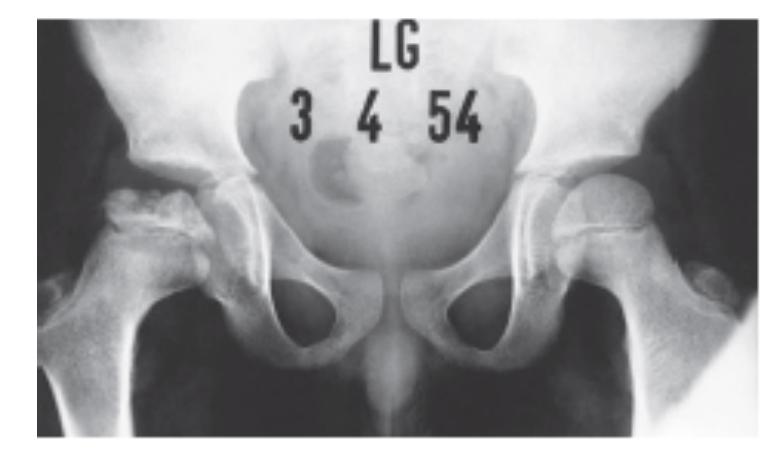

A 15-month-old child was brought to the clinic because of painless limping. There is no history of trauma. The pelvic x-ray is shown.

Q1: Write two abnormalities seen on the X-ray.

- Lateralization of the ossifying centre

- Acetabular angle more than 27ยฐ

- Broken Shenton line

- Shortening of the line from greater trochanter to the horizontal line

Q2: What is the most probable diagnosis?

- Developmental dysplasia of the hip (DDH)

10 months old child presenting with this condition:

- Right DDH